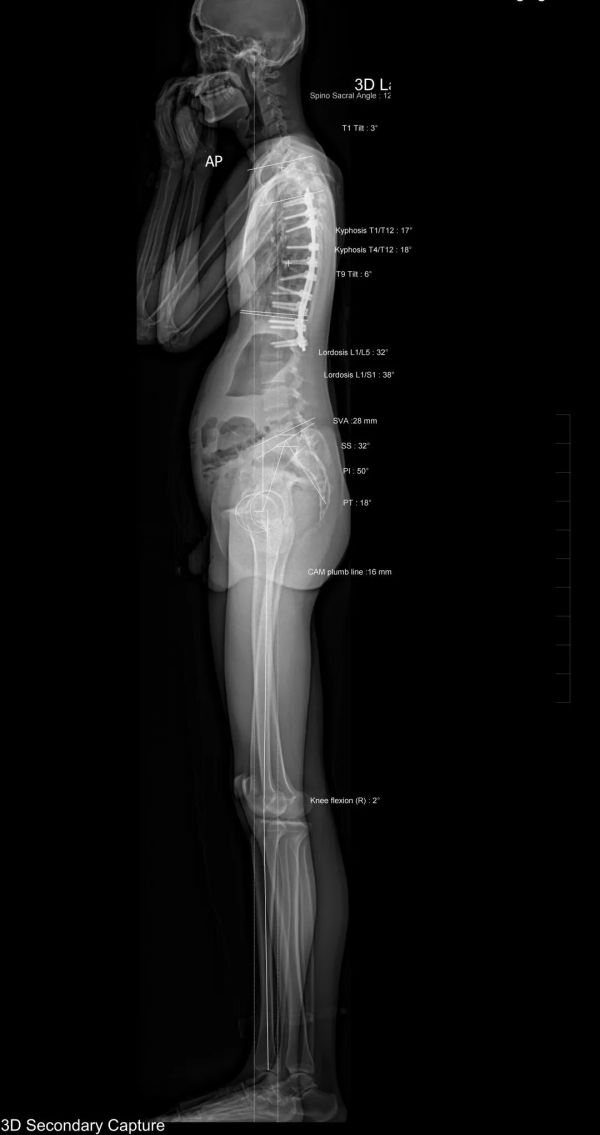

EOS全身正側(cè)位

原“胸7、11、12蝴蝶椎體畸形,胸6-8、胸10-11阻滯椎,脊椎側(cè)彎術(shù)后”患者復(fù)查,對(duì)比2022.07.25老片,現(xiàn)片示:

胸4-腰2見(jiàn)金屬內(nèi)固定影,其形態(tài)、位置未見(jiàn)異常。脊柱“S”型側(cè)彎較前糾正,脊柱胸椎多發(fā)椎體形態(tài)不規(guī)整同前,胸椎部分椎間隙顯示欠清。骨盆稍向右側(cè)傾斜,左髖白較右髖臼高約5mm。

測(cè)量參數(shù)如下:脊柱矢狀位測(cè)量如下:胸椎后凸角 (T1/T12)約17°,腰椎前凸角 (L1/L5)約32°,矢狀面軸向距離 (SVA) 28mm,骨盆入射角(FI)約50°。

雙側(cè)下肢長(zhǎng)度測(cè)量如下:右側(cè)股骨頭中心至-脛骨下穹隆長(zhǎng)度約829mm,左側(cè)長(zhǎng)度約827mm。右膝關(guān)節(jié)向中心線外側(cè)偏離Mikulicz線12mm。